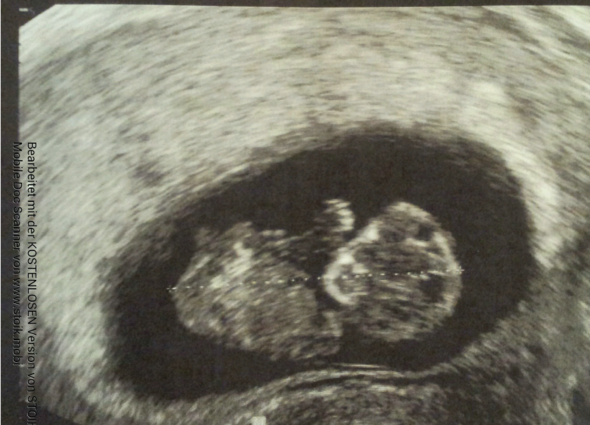

Bin nach einer ICSI schwanger geworden 1 hcg Wert aus dem Blut bei ES 15 war 452, 2 hcg bei ES19 2128 Gstern hatte ich nun bei 51 meinen ersten Ultraschall Der Arzt hat 2 Fruchthöhlen von je 5mm gesehen aber noch ohne "Inhalt" Ich soll jetzt in 10 en wieder hin da müsse man das oder die Herzchen schlagen sehen.

Frühe Zwillingsschwangerschaften im Ultraschall Eineiige Zwillinge in der 55 Schwangerschaftswoche Schwangerschaften entstehen – und das ist nun wirklich nicht überraschend neu – nachdem eine Eizelle von einem Samenfaden befruchtet wurde Zwillinge können auf zwei Arten entstehen. Ultraschall 5 SSW Rechts im Bild ist die Fruchthöhle (schwarz) zu sehen Der Embryo ist jetzt etwa zwei Millimeter lang und auf dem Ultraschall zu dieser Zeit oft noch nicht zu erkennen Trotzdem beginnt in dieser Woche das Herz des Embryos zu schlagen. Sie sind in SSW 4 (SSW 4 06) oder in der 5 Schwangerschaftswoche Jetzt können Sie einen Schwangerschaftstest machen!.

Ultraschallbild 53 SSW Ein Ultraschallbild aus dem 3 der 6 Schwangerschaftswoche (53) Dieser Befund ist eher typisch für die Mitte der sechsten SSW Meist stellt sich die Fruchthöhle nun nicht mehr ganz rund wie in der 5 SSW dar, sondern erscheint leicht queroval. Heute war ich dann wieder zum Termin man sah im Ultraschall eine kleine Fruchthülle Zudem wurde wieder Blut Abgenommen und eben rief mein Frauenarzt mich an und sagte mir mein Hcg Werte 56 ssw;. Re Ultraschall 65 ssw Antwort von ZavaMamy am , 2230 Uhr Mir ging es so ähnlich mit den Anzeichen Es ist meine 4 Schwangerschaft und dieses mal war ich wesentlich müder, die Nase empfindlicher und mir war viel übler als die Maler davor.